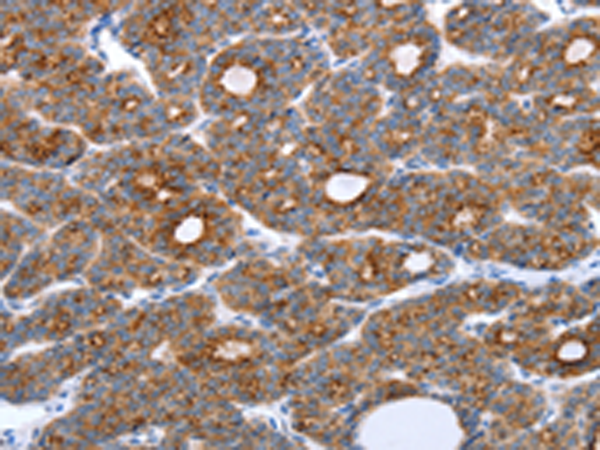

分类: 科研抗体货号: P11131别名: SELS; VIMP; ADO15; SBBI8; SEPS1; AD-015应用: IHC反应种属: Human, Mouse, Rat